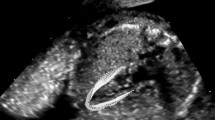

All echocardiograms were performed by a single investigator and according to the practice guidelines and recommendations of the Writing Group of the American Society of Echocardiography in collaboration with the European Association of Echocardiography and the Association for European Pediatric Cardiologists [13]. A Vivid S70 device was used (GE Healthcare, Horten, Norway) with a 4.0–12.0 MHz phased-array transducer.

RV and LV systolic function was quantitatively assessed by measuring peak RV free wall and global longitudinal strain (RV FWLS and RV GLS) and LV global longitudinal strain (GLS) by two-dimensional speckle tracking echocardiography (2D STE) from the RV- and LV-focused apical four chamber view [10]. The frame rate of image acquisition was 96 frames per second for a frame rate-to-heart rate ratio between 0.7 and 0.9 frames per second per beat per minute. We chose to include the septum in the measurement of LV function as part of the GLS because although it contributes to the function of both ventricles, it is currently regarded as part of the LV [15, 16].